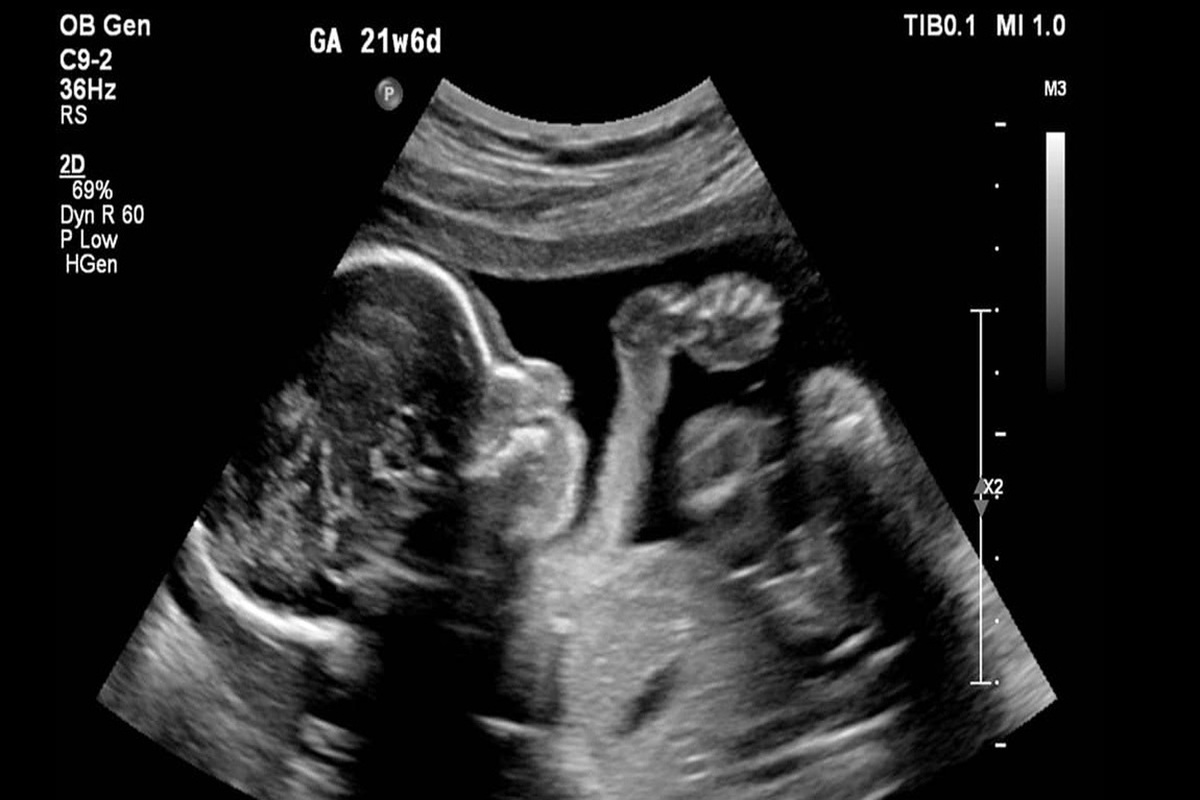

چند درصد آمار سقط جنین در کشور؛ غیرقانونی و نامشروع است؟

به گفته این پژوهشگر حوزه جمعیت، از حدود ۹۴ تا ۹۵ درصد سقط غیرقانونی ۳ تا ۴ درصد ناشی از روابط نامشروع و خارج از عرف و خانواده است اما ۹۱ تا ۹۲ درصد سقط جنین‌ها محصول نهاد خانواده مشروع است و این جای نگرانی بسیاری دارد.

همشهری آنلاین نوشت: بر اساس مطالعات انجام شده در کشور، به طور میانگین سالانه بین ۳۵۰ تا ۵۳۰ هزار سقط در کشور انجام می‌شود و تقریبا یک سوم تولدها در کشور از دست می‌رود. از این تعداد تنها حدود ۱۰ تا ۱۲ هزار سقط با مجوز قانونی و از سوی پزشکی قانونی انجام می‌شود.

آمارهای سقط جنین در کشور نگران‌کننده است و همزمان با آن آمار تولد در کشور هم روند کاهشی دارد. از حدود یک میلیون تولد در سال ۹۹ به یک میلیون و ۱۰۰ تولد در ۱۴۰۱ رسیده است. رئیس‌جمهوری هم اواخر فروردین آمارهای ارائه شده درباره سقط جنین را نگران‌کننده دانست و بر ضرورت اهتمام وزارت بهداشت نسبت به این موضوع و هماهنگی بیشتر با دستگاه قضایی برای برخورد با متخلفان در این زمینه تأکید کرد. بر اساس اعلام وزارت بهداشت بیش از ۸۰ درصد سقط جنین‌های غیرقانونی در خارج از مراکز درمانی و عمده آنها در خانه‌ها و از طریق قرص‌های خونریزی‌دهنده صورت می‌گیرد.

صالح قاسمی، دبیر مرکز مطالعات راهبردی جمعیت با بیان این که سقط جنین ابعاد مختلفی دارد، درباره آمارهای این پدیده به همشهری آنلاین گفت: به طور میانگین سالانه ۳۵۰ هزار تا ۵۳۰ هزار مورد سقط جنین در کشور انجام می‌شود که از این میزان حدود ۱۰ تا ۱۲ هزار مورد مجوزدار است و توسط پزشکی قانونی انجام می‌شود. حدود ۱۰ تا ۱۲ هزار مورد هم سقط غیرارادی است و بقیه آن سقط غیرقانونی و جنایی است که شامل دو دسته می‌شود.